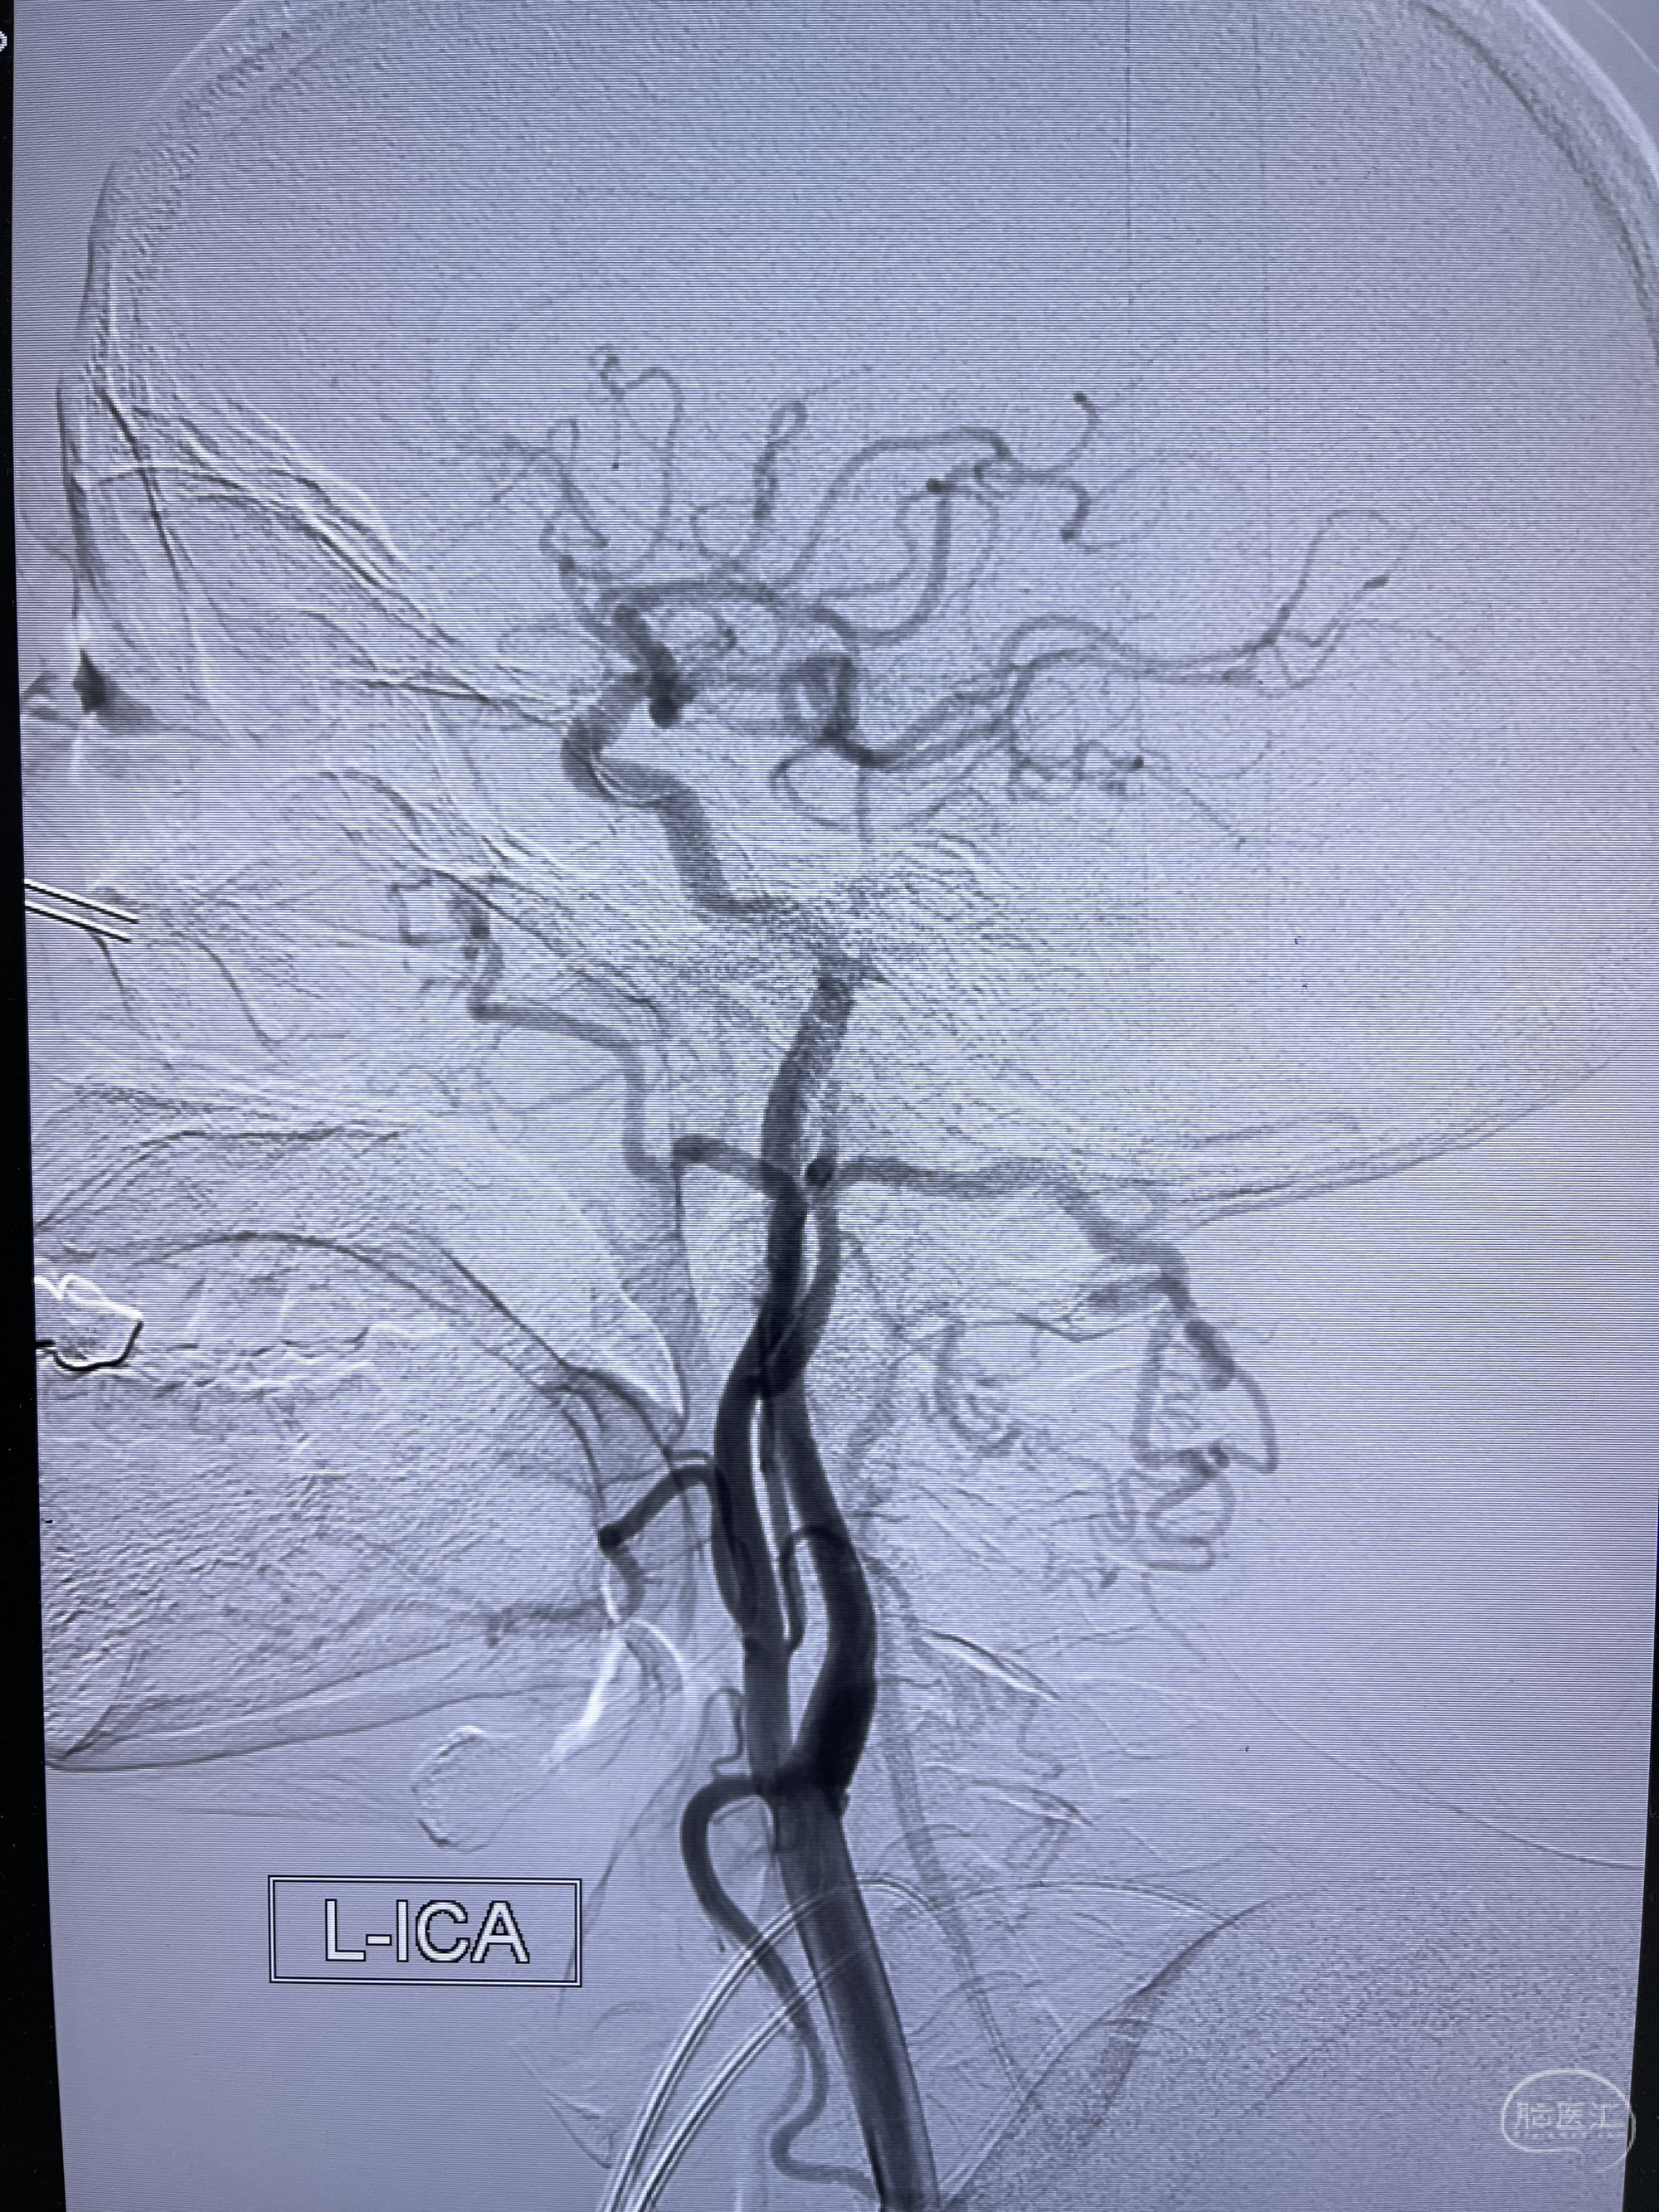

患者,男,70岁。因为“左侧颈动脉支架成形术后近3年,发现右侧颈内动脉瘤3月”入院。

患者2019-03因左侧颈内动脉狭窄伴脑梗死至复旦大学附属中山医院青浦分院就诊,行左侧颈动脉球囊扩张支架植入术,术后患者恢复可;后于2019-09-24复查脑血管造影,未见狭窄复发;2022-01-15于上海市松江区中山街道社区卫生服务中心复查颈动脉超声提示:右侧颈内动脉闭塞,双侧颈动脉斑块;患者无明显不适,遂继续随访;2022-11-21患者再次行左侧颈动脉支架植入术后复查,头颅CTA提示:左侧颈总动脉起始部支架植入状态,管腔通畅,右侧颈内动脉颈段及岩骨段闭塞,右侧颈内动脉破裂孔段动脉瘤。现患者偶有右侧肢体麻木,伴左下肢活动不利,步态不稳,为求进一步治疗颅内动脉瘤至我科就诊,收治入院。

2022-11-21 上海市松江区中心医院 头颅CTA:左侧颈总动脉起始部支架植入状态,管腔通畅,右侧颈内动脉颈段及岩骨段闭塞,右侧颈内动脉破裂孔段动脉瘤。

5.左侧颈总动脉起始部支架术后